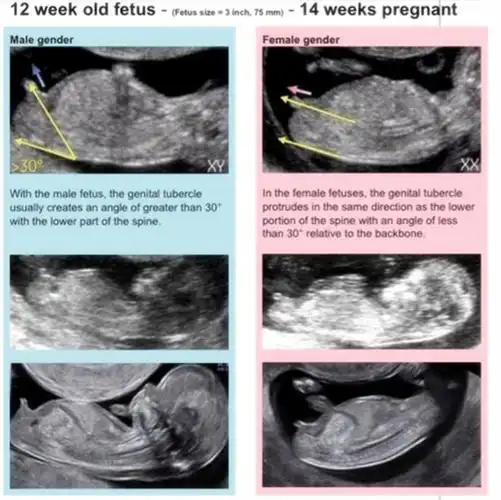

[试管婴儿]nt和13周拍的b超.大家帮忙看看nub点是男是女?

13周nt归来,有没有懂nub理论的姐妹帮看男女呢?